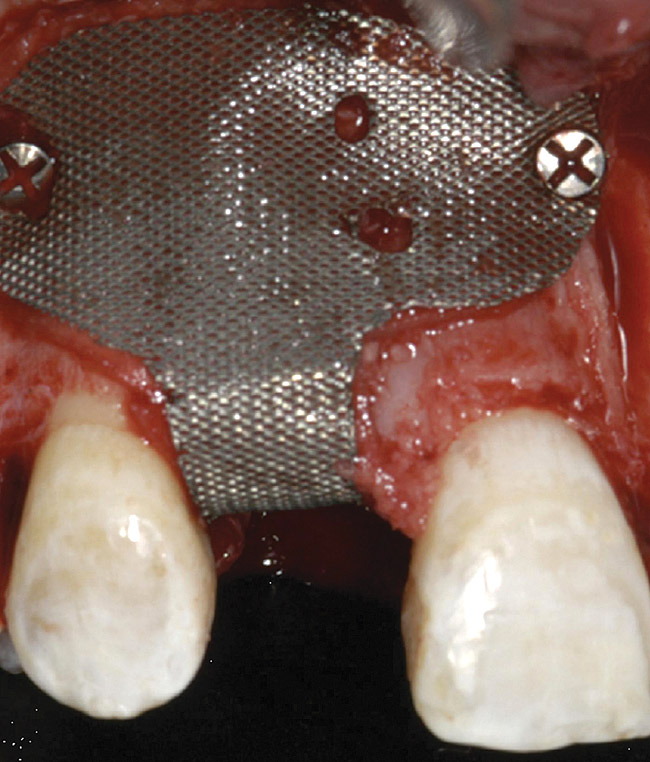

A 16-year-old female patient with a congenitally missing maxillary right lateral incisor was referred for an implant-supported crown. Clinical and CBCT evaluation revealed both a facial and palatal bony width deficiency (Figure 2 and Figure 3). The treatment plan included the use of titanium mesh and rhBMP-2/ACS (INFUSE® Bone Graft) along with mineralized allograft (MinerOss®, BioHorizons, www.BioHorizons.com) for bony augmentation (Figure 4 and Figure 5). After 7 months, the graft was found to be well incorporated and allowed for placement of a 3.8-mm x 10.5-mm diameter root form implant that was restored 3 months later (Figure 6, Figure 7, Figure 8, Figure 9 and Figure 10).

Figure 5  Titanium mesh/particulate graft complex.

Figure 5